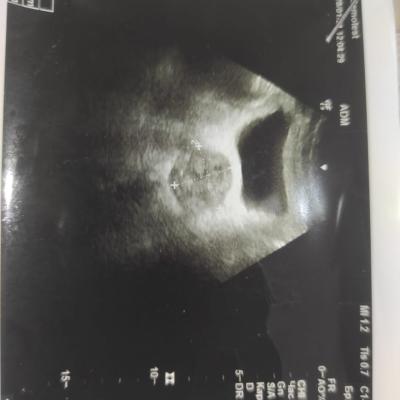

Здравствуйте! При наличии коралловидного камня правой почки(заключение УЗИ), можно предположить причиной боли нарушение уродинамики верхних мочевых путей), что, однако, не подтверждается результатами УЗИ почек( ЧЛС не расширена). Другая, наиболее вероятная возможная причина "боли в боку" - может быть патология опорнодвигательного аппарата. Необходимо проконсультироваться с неврологом и урологом очно, и согласовать возможность применения противовоспалительных, обезболивающих и спазмолитических препаратов - как первый шаг. В дальнейшем необходимо планировать возможное дальнейшее обследование и лечение. Удачи!